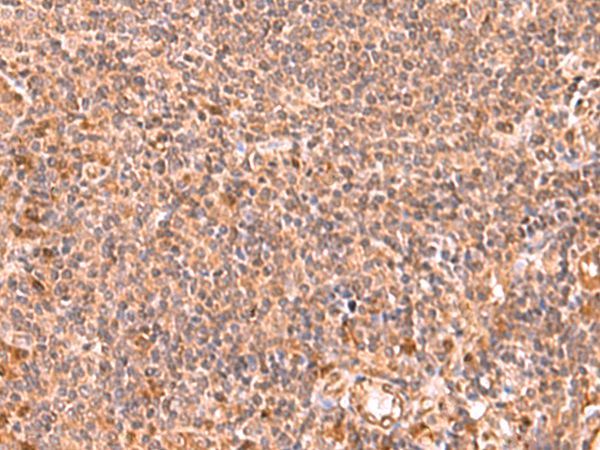

分类: 科研抗体货号: P10117别名: RTA; fxh; FOX2; RBM9; Fox-2; HNRBP2; HRNBP2; dJ106I20.3应用: IHC反应种属: Human, Mouse, Rat